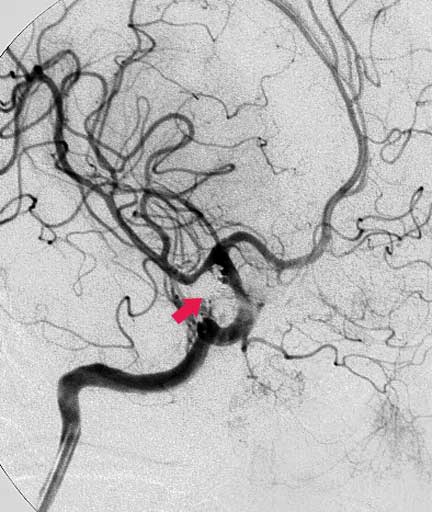

CASO 1 : Embolización endovascular de aneurismas con microespiras (coils) en paciente anciano y de alto riesgo para cirugía abierta

Angiografía antes de la embolización

Angiografía después de laembolización la cual muestra cierre completo del aneurisma